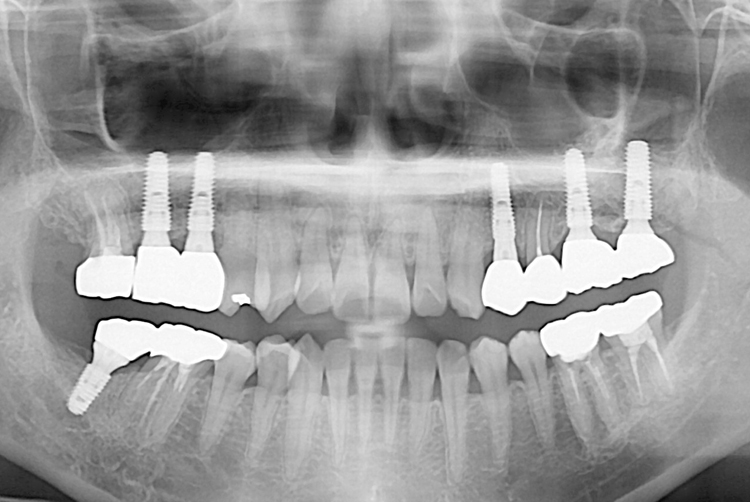

[임플란트] 임플란트

치료전 : 2018-06-14

세종치과는 많은 환자와 다양한 케이스를 바탕으로 항상 편안한 임플란트 수술을 제공하고자 노력하고,

오래동안 튼튼히 쓸 수 있는 임플란트 수술을 가장 큰 목표로 삼고 있습니다